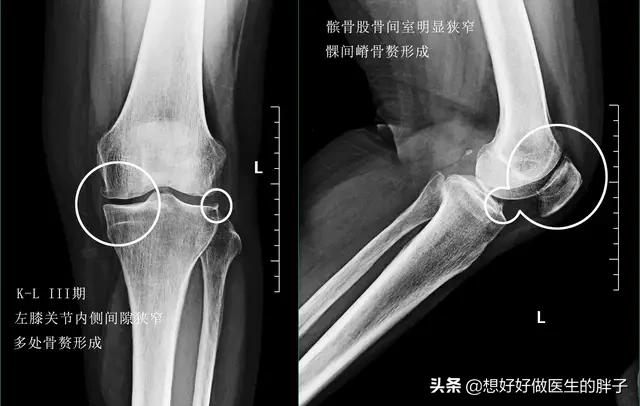

到了关节软骨磨损的晚期,很可能关节内负重区的软骨已经被磨得消失殆尽了。所以患者的关节往往会出现明显的间隙狭窄和大量的骨赘形成,此时的患者,严重的关节屈伸角度也会有明显的受限,而且疼痛会对患者的整个生活导致非常大的困扰,有些比较重的患者甚至会出现休息的时候关节也疼痛,而且在夜间休息的时候能疼醒,此时以前的一些治疗方法就很难帮助患者解决问题了,进行关节置换或者是部分关节置换,是解决患者问题的最佳措施(康复锻炼一样要做)。